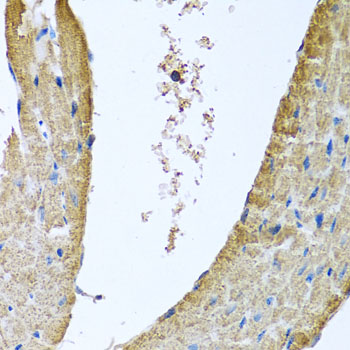

Immunohistochemistry of paraffin-embedded mouse heart using COX5B at dilution of 1:100 (40x lens).